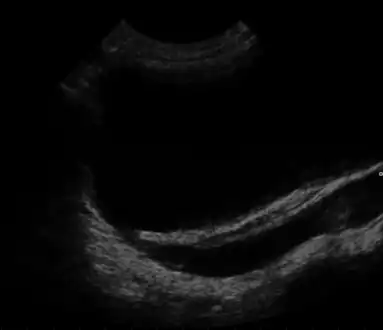

Ultrasound showing vesicoureteral reflux

Ultrasound showing vesicoureteral reflux

The cause includes a numbers of genetic mutations and exposure to certain drugs or medications during pregnancy.[1] The underlying mechanism involves urine being unable to flow through the tubules within the kidneys resulting in cyst formation.[1] Diagnosis is generally by ultrasound, either before or after birth.[1]

MCDK is usually diagnosed by ultrasound examination before birth. Mean age at the time of antenatal diagnosis is about 28 weeks[10] A microscopic analysis of urine in individuals with probable multicystic dysplastic kidney should be done.[8]One meta-analysis demonstrated that unilateral MCDK occurs more frequently in males and the greater percentage of MCKD occur on the left side of the body.[11]